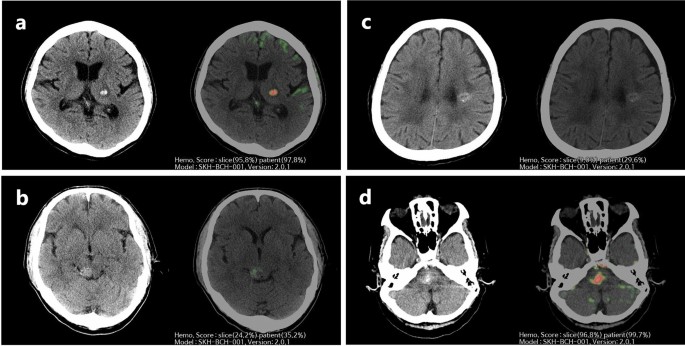

Therefore, a total of 288 complete CT images (CCM, n = 173; AIH, n = 115) that satisfied the criteria for image analysis were enrolled in the study. The CT images were processed using the AI algorithm, generating heatmaps and probability scores through slicewise and patientwise analysis, highlighting possible hemorrhage locations. These results were displayed alongside the original CT images on the PACS viewer (Fig. 2).

Representative images of the AI algorithm for differentiating CCM and AIH. AI, artificial intelligence; CCM, cerebral cavernous malformation; AIH, acute intraparenchymal hemorrhage; CT, computed tomography. (a) Brain CT shows AIH in the left thalamus. AI-assisted brain CT analysis provided probability scores of hemorrhage in a slicewise (95.8%) and patientwise (97.8%) manner. All six reviewers correctly interpreted the images as AIH for both AI-unassisted and AI-assisted interpretations. (b) Brain CT shows a CCM on the right side of the midbrain. AI-assisted brain CT analysis provided a probability score of hemorrhage in a slicewise (24.2%) and patientwise (35.2%) manner. One radiology resident and one emergency department physician incorrectly interpreted the images as AIH in the AI-unassisted brain CT. However, with the use of AI assistance, all reveiwers correctly diagnosed the images as CCM. (c) Brain CT shows a CCM in the left corona radiata. AI-assisted brain CT analysis generated probability scores of hemorrhage in a slicewise (9.0%) and patientwise (29.6%) manner. All six reviewers accurately identified the images as CCM for both AI-unassisted and AI-assisted interpretations. (d) Brain CT shows AIH in the pons. AI-assisted brain CT analysis generated a probability score of hemorrhage in a slicewise (96.8%) and patientwise (99.7%) manner. All neuroradiologists and emergency department physicians erroneously interpreted the images as CCM in the AI-unassisted brain CT. Nevertheless, with the use of AI assistance, all reviewers accurately diagnosed the images as AIH.